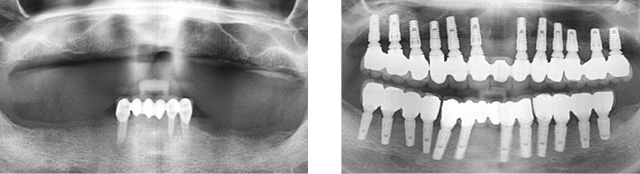

상악틀니를 사용 중 저작력이 약한 환자분. 대학병원에서 전체 임플란트를 받으시려 했으나 비용 문제로 고운미소로 내원하셨습니다. 당뇨수치가 있어 내과와 연계하여 식생활 조절과, 운동, 인슐린 치료를 병행하여 충분한 혈당관리를 하고 임플란트 수술을 시행하였습니다.

임플란트를 지지하기 위한 뼈의 상태가 좋지 않아, 상악동 뼈 이식과 함께 총 24개의 임플란트를 식립하였습니다. 전체 임플란트가 완성된 이후에도 내과와 지속적인 연계로 전신건강이 회복될 수 있게 노력해야 합니다.